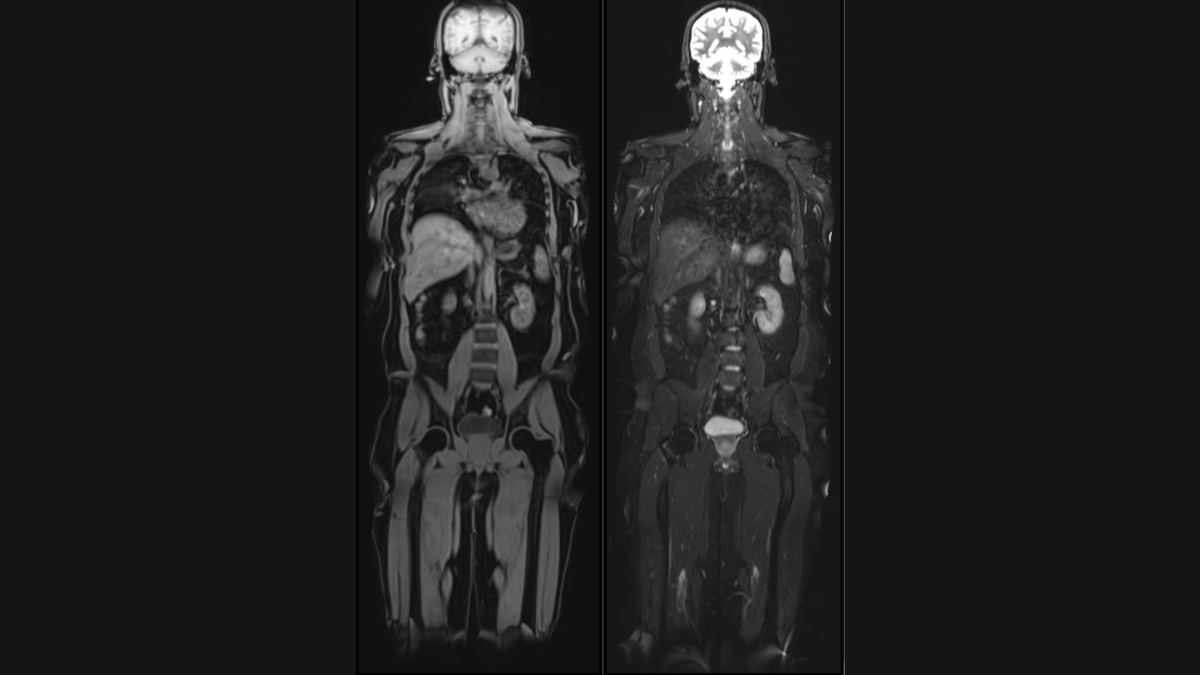

New Delhi [India], August 29: Aarthi Scans and Labs, a leading name in medical diagnostics, today announced the launch of its groundbreaking new unit, ‘Vital MRI.’ This innovative service offers comprehensive full body MRI scans at an affordable cost of ₹24,000, empowering individuals to take proactive steps towards their long-term health.

Vital Full Body MRI aims to detect potential health issues at their earliest stages, including early-stage cancers, aneurysms, spinal degeneration, disc bulges, and abnormalities in the brain, abdomen, and chest. The scans utilize cutting-edge technology to provide detailed, high-resolution images, enabling early diagnosis and intervention, thereby improving treatment outcomes.

Unique offerings of Vital MRI are – Brain volume analysis, Liver fat and Visceral fat quantification by MRI and Calcium scoring CT to assess heart attack risk. Brain volumetry analysis, generating a ‘Brain Age’ report that compares an individual’s brain health to their chronological age. This valuable insight can help individuals understand their cognitive well-being and take proactive measures to maintain brain health and prevent dementia.

“Similar facilities are available in the US through providers like Prenuvo and Ezra, but we are proud to be the first to offer this level of comprehensive and affordable preventive scanning in India. Most cancers, when detected in stage I, have very good prognosis and can even be completely cured with modern treatments. With Vital MRI, we aim to empower individuals to take control of their health and detect potential issues before they become serious” said Dr Arunkumar Govindarajan, Radiologist and Executive Director of Aarthi Scans and Labs.